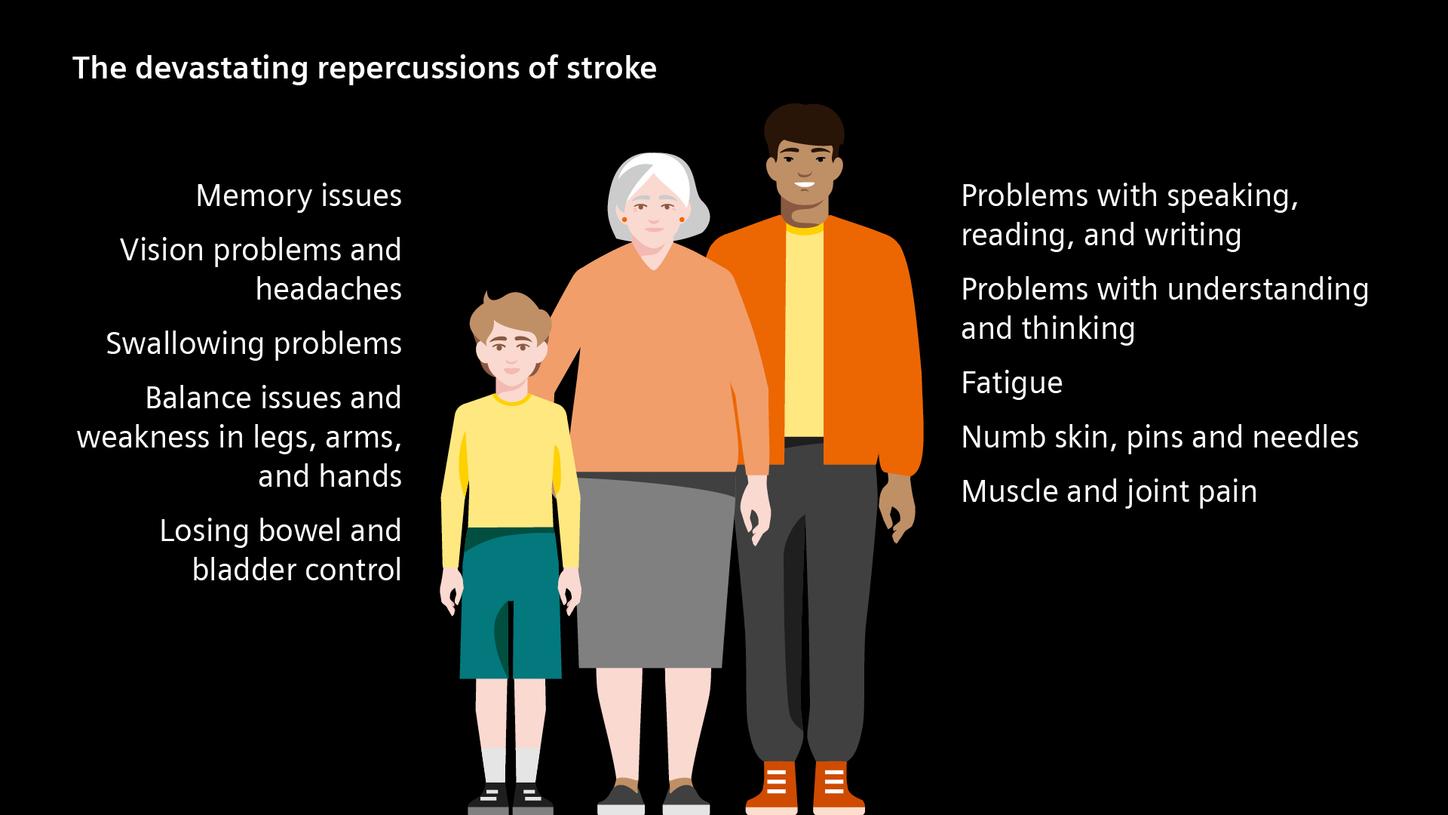

Aftercare

Strong again – long-term care and secondary stroke prevention